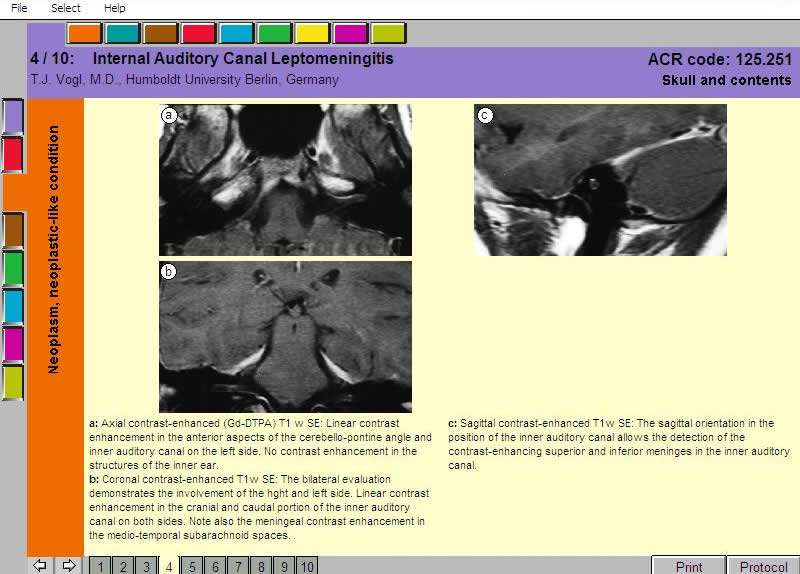

afbeelding van een scherm:

MRI